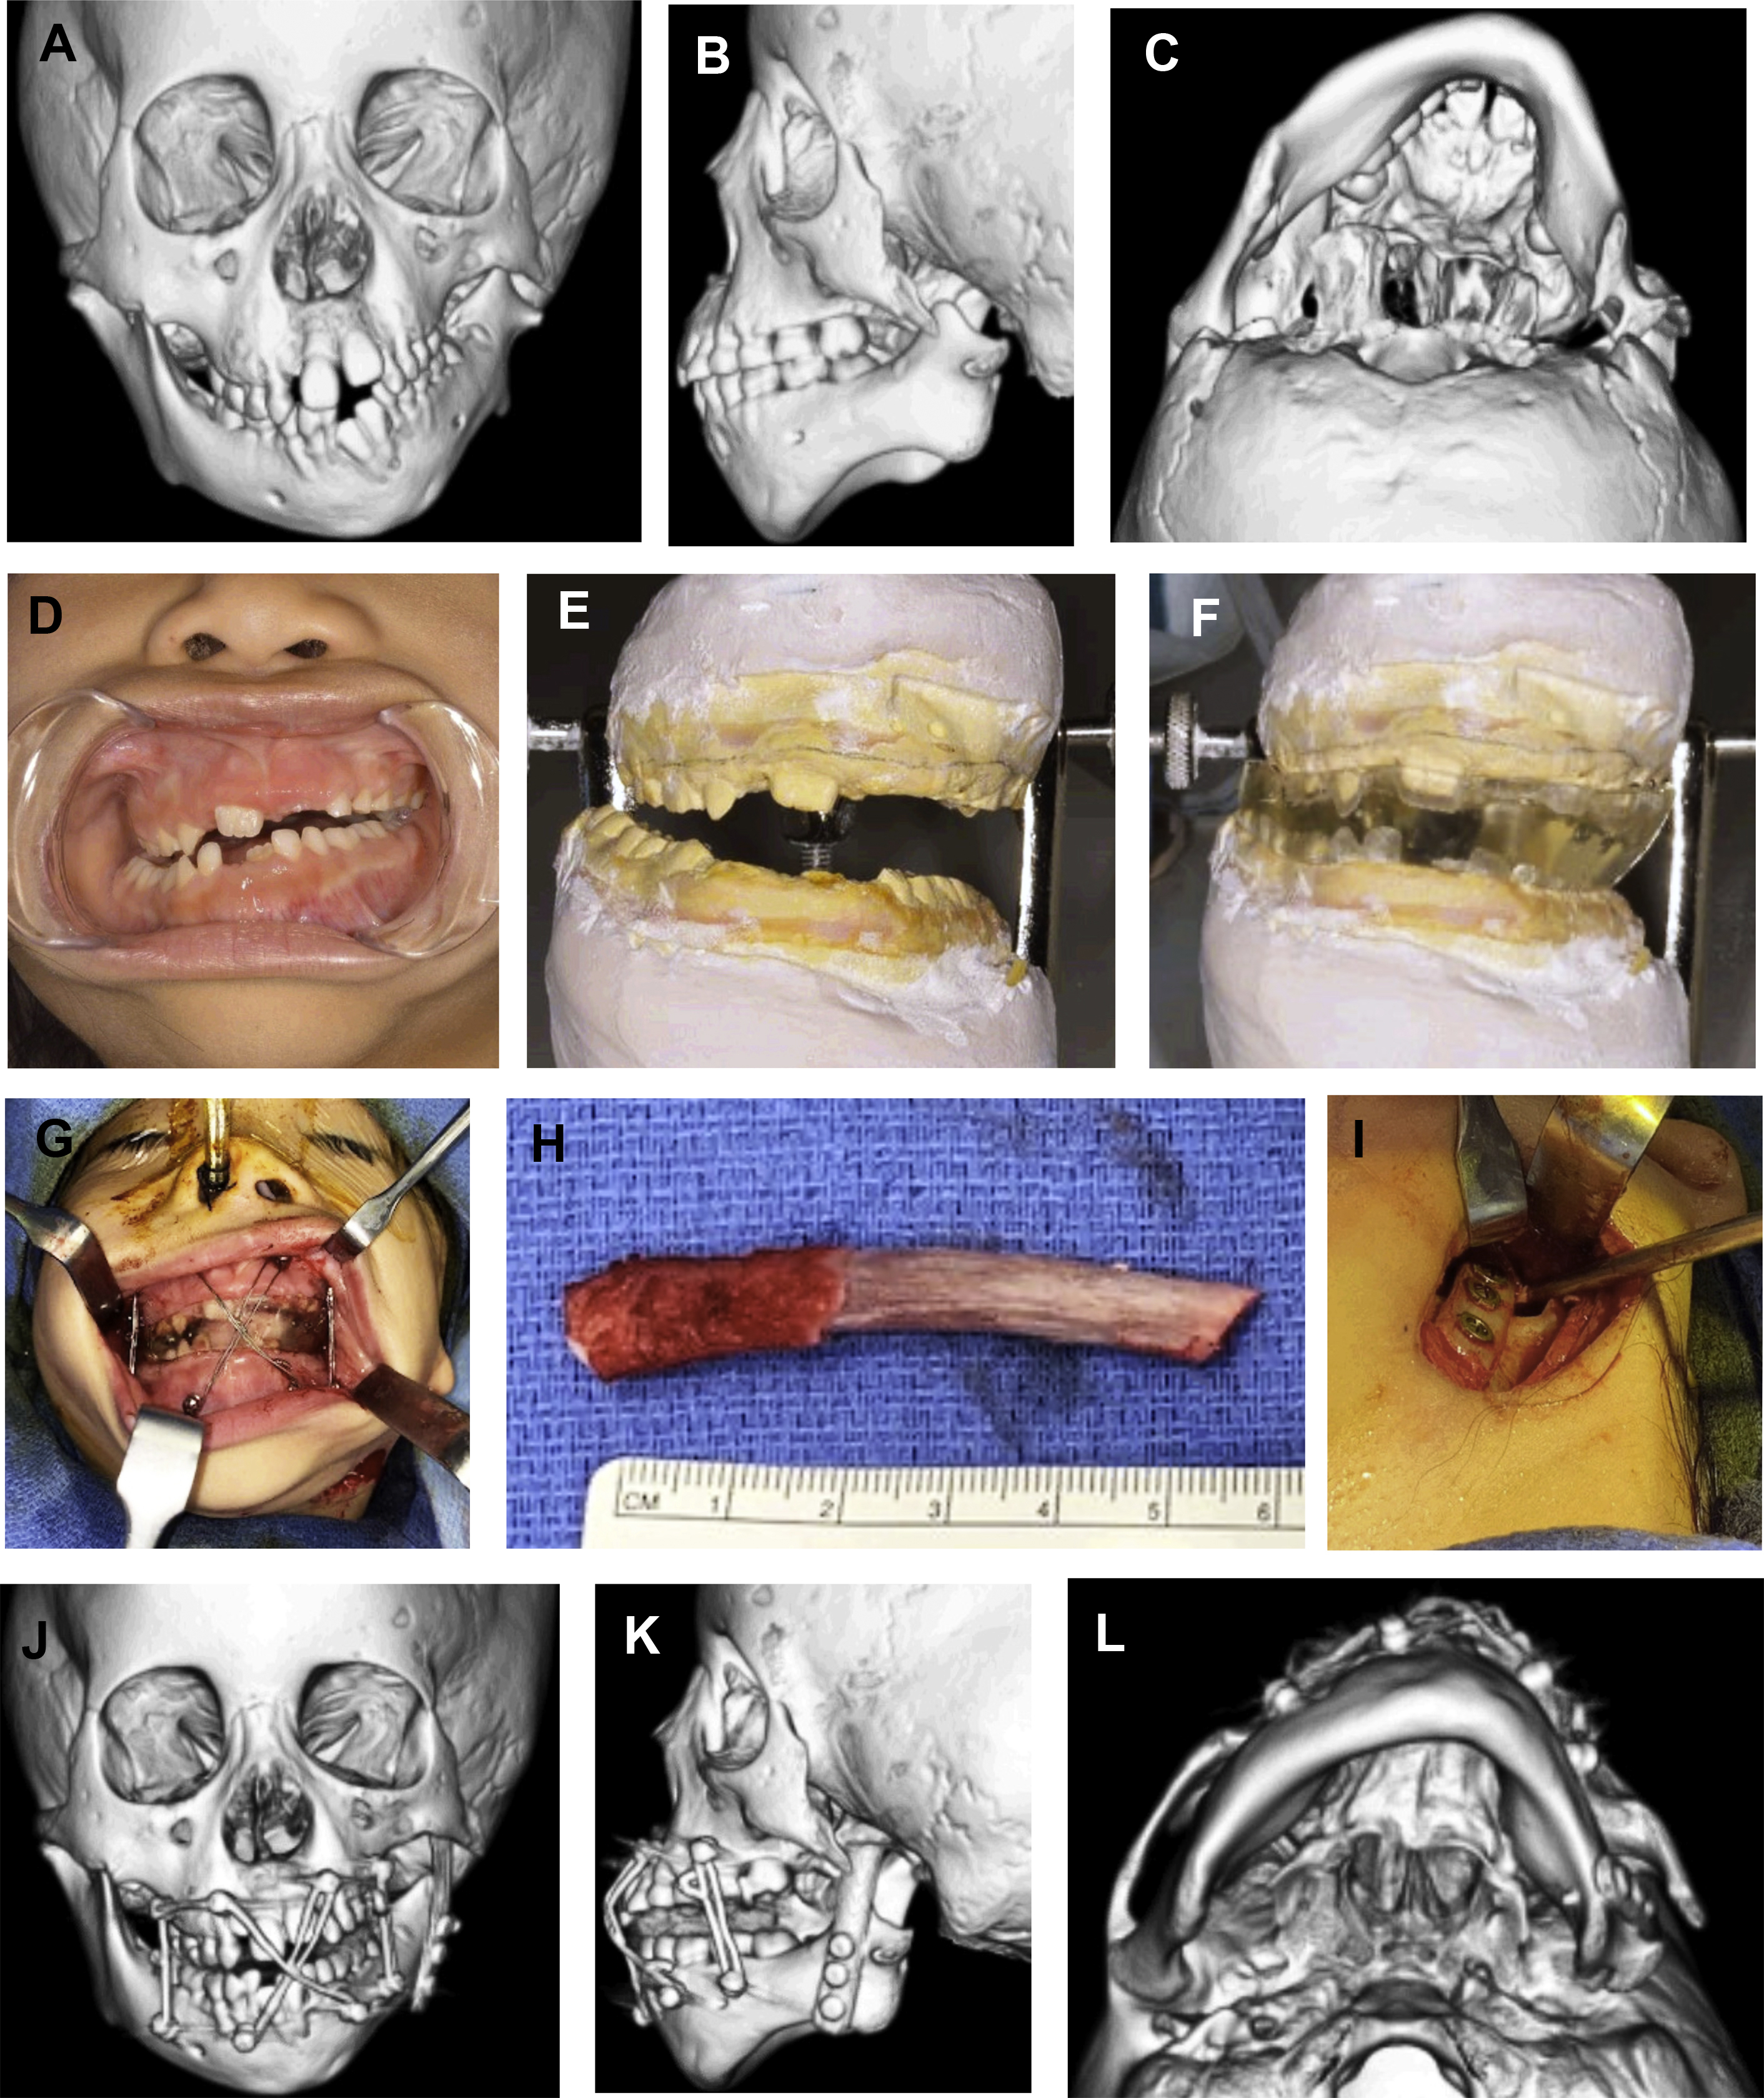

The goals of costochondral grafting for reconstruction in children with Pruzansky type IIB and III mandibles include (1) reconstruction of a new ramus and pseudocondyle; (2) generation of a pseudarthrosis by placing the rib graft in a pocket abutting the cranial base; (3) alignment of the maxillomandibular dental midlines with the midsagittal plane; and (4) correction without overcorrection of the mandibular cant, consequently restoring facial asymmetry with the assumption of ongoing rib growth. Surgical management begins in the orthodontic clinic with preoperative fabrication of an occlusal splint based on predicted final mandibular position and large posterior open bite. Alternatively, the splint may be created intraoperatively using polymethylmethacrylate or virtually planned using three-dimensional CT technology. We have previously described our technique for costochondral rib grafting, which broadly consists of (1) rib harvest, (2) neofossa creation, and (3) postoperative orthodontic splint therapy ( Fig. 2 ).